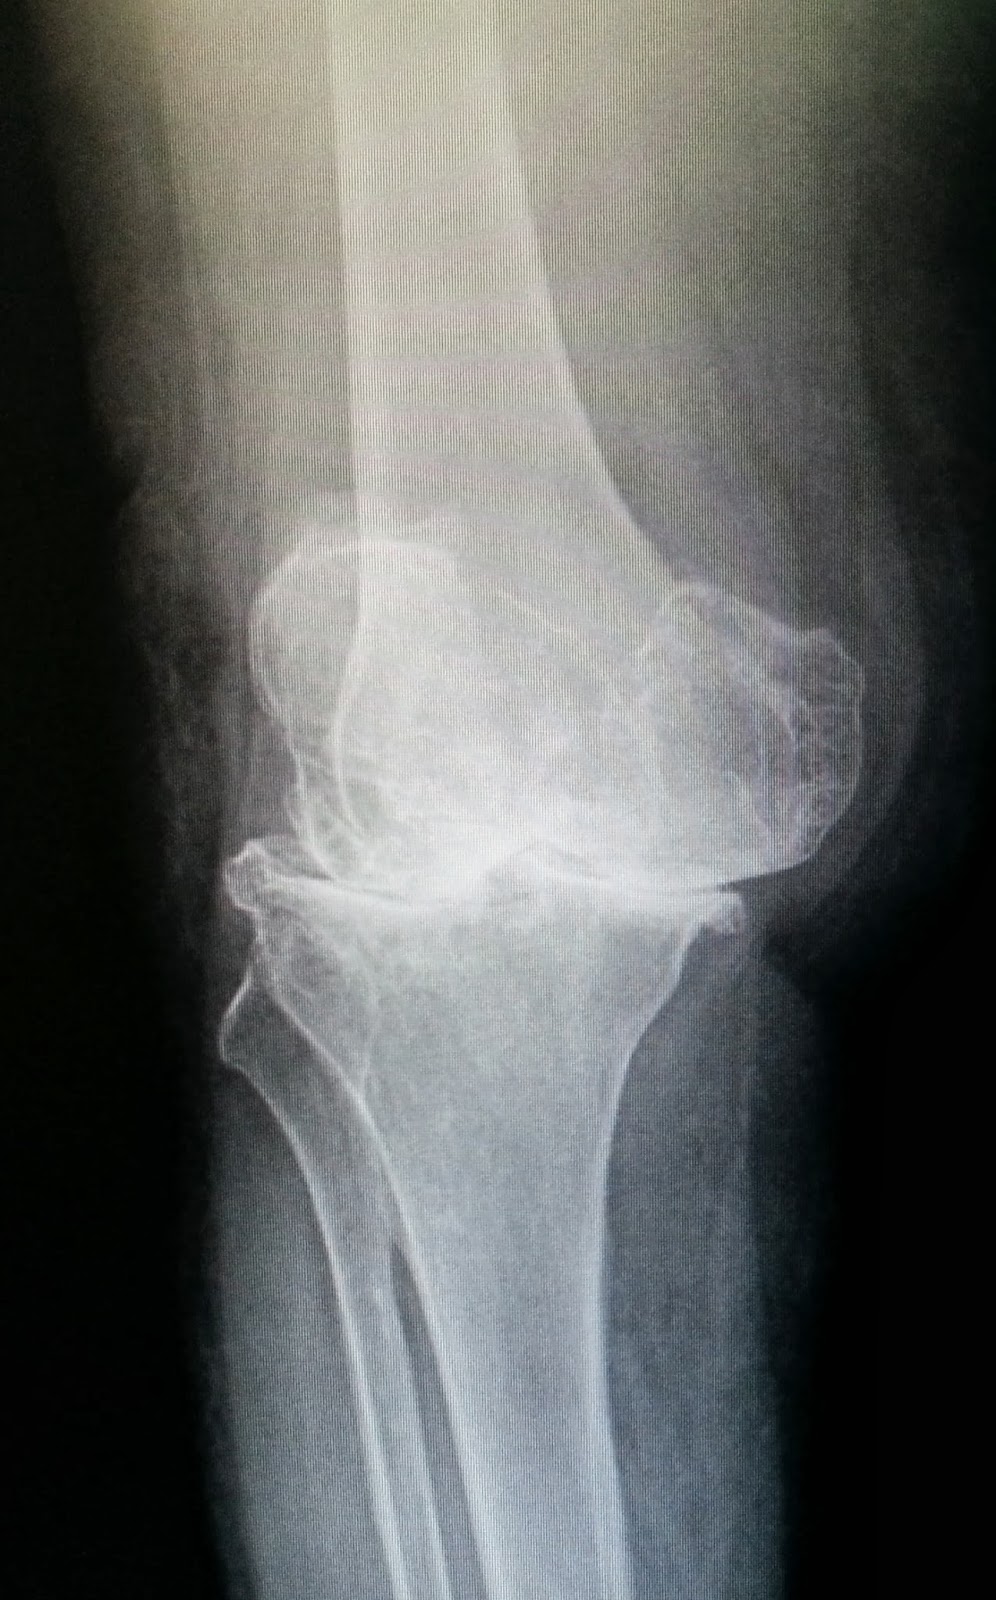

โรคข้อเข่าเสื่อมนับว่าเป็นปัญหาที่สำคัญอย่างหนึ่งในผู้สูงอายุ คนไทยเป็นโรคข้อเข่าเสื่อมมากกว่า 6 ล้านคน ผู้ป่วยมักจะมีอาการปวดเข่า โดยเฉพาะเวลาเดิน ขาโก่งผิดรูป ปัจจัยสำคัญที่ทำให้อาการเข่าเสื่อมเป็นมากขึ้นมักพบในคนอ้วน ร่วมกับกิจวัตรประจำวันที่มีการงอเข่ามากเกินไป เช่น การนั่งยองๆ การนั่งขัดสมาธิ การนั่งพับเพียบ มักจะเกิดคำถามขึ้นมากมายเกี่ยวกับการรักษาโรคข้อเข่าเสื่อมด้วยการผ่าตัดเปลี่ยนข้อเข่าเทียม

2. ในกรณีที่ผู้ป่วยมีขาโก่งมากๆ แพทย์มักจะแนะนำให้ผู้ป่วยทำการรักษาด้วยวิธีการผ่าตัดเปลี่ยนข้อเข่าเทียม เนื่องจากว่าในผู้ป่วยที่ขาโก่งผิดรูป มากๆ นั้นจะมีผลทำให้เดินลำบาก การทรงตัวของผู้ป่วยเสียไป เดินได้ไม่ดี มีโอกาสหกล้มได้ง่าย และอาจจะเกิดกระดูกหักตามมา นอกจากนั้นขาที่โก่งที่ทำให้เกิดการเดินที่ผิดปกติ ยังมีผลต่อสมดุลของร่างกาย ทำให้มีการกระจายน้ำหนักของร่างกายผิดปกติไปโดยเฉพาะที่บริเวณกระดูกสันหลัง จึงมักจะทำให้ผู้ป่วยมีอาการปวดหลังเพิ่มมากขึ้น และในบางครั้งผู้ป่วยอาจจะมีอาการปวดหลังและชาร้าวลงขา ร่วมกับอาการปวดเข่าเนื่องจากโรคข้อเข่าเสื่อมด้วย